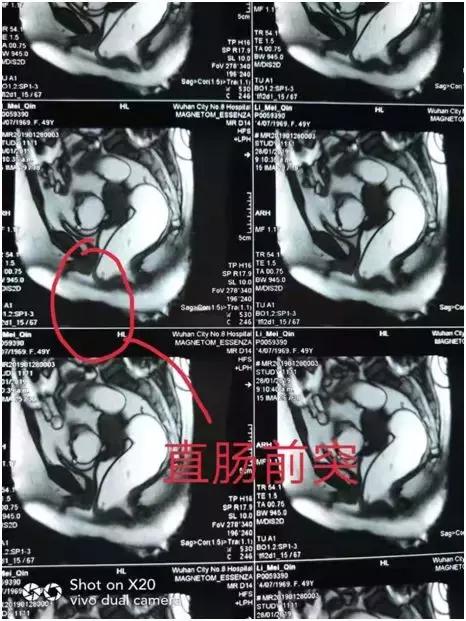

2月23日,光山县人民医院普外科陆永广团队在河南中医药大学第一附属医院肛肠诊疗中心张向安主任的指导下,成功对一位出口梗阻性便秘的患者行外科手术治疗,并诊断出口梗阻性便秘是由于直肠前突及耻骨直肠肌肥厚造成,遂采取经肛直肠前突修补术+耻骨直肠肌松解挂线器挂线术+直肠粘膜硬化剂注射术,手术取得了不错的效果。